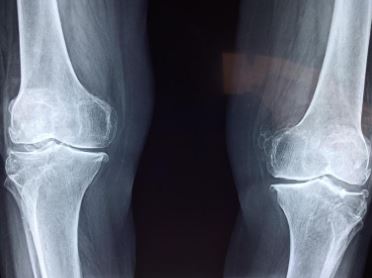

산양유는 뼈 건강에 도움을 줄 수 있습니다. 실제로 산양유 단백질 섭취 시에 골밀도에 어떤 변화가 생기는지 알아보는 연구 결과가 있습니다. 난소 절제술을 받은 쥐에게 19주 동안 산양유 단백질을 공급한 결과, 허리뼈의 골밀도와 대퇴골의 골질 함량이 상승하는 것이 확인되었습니다.